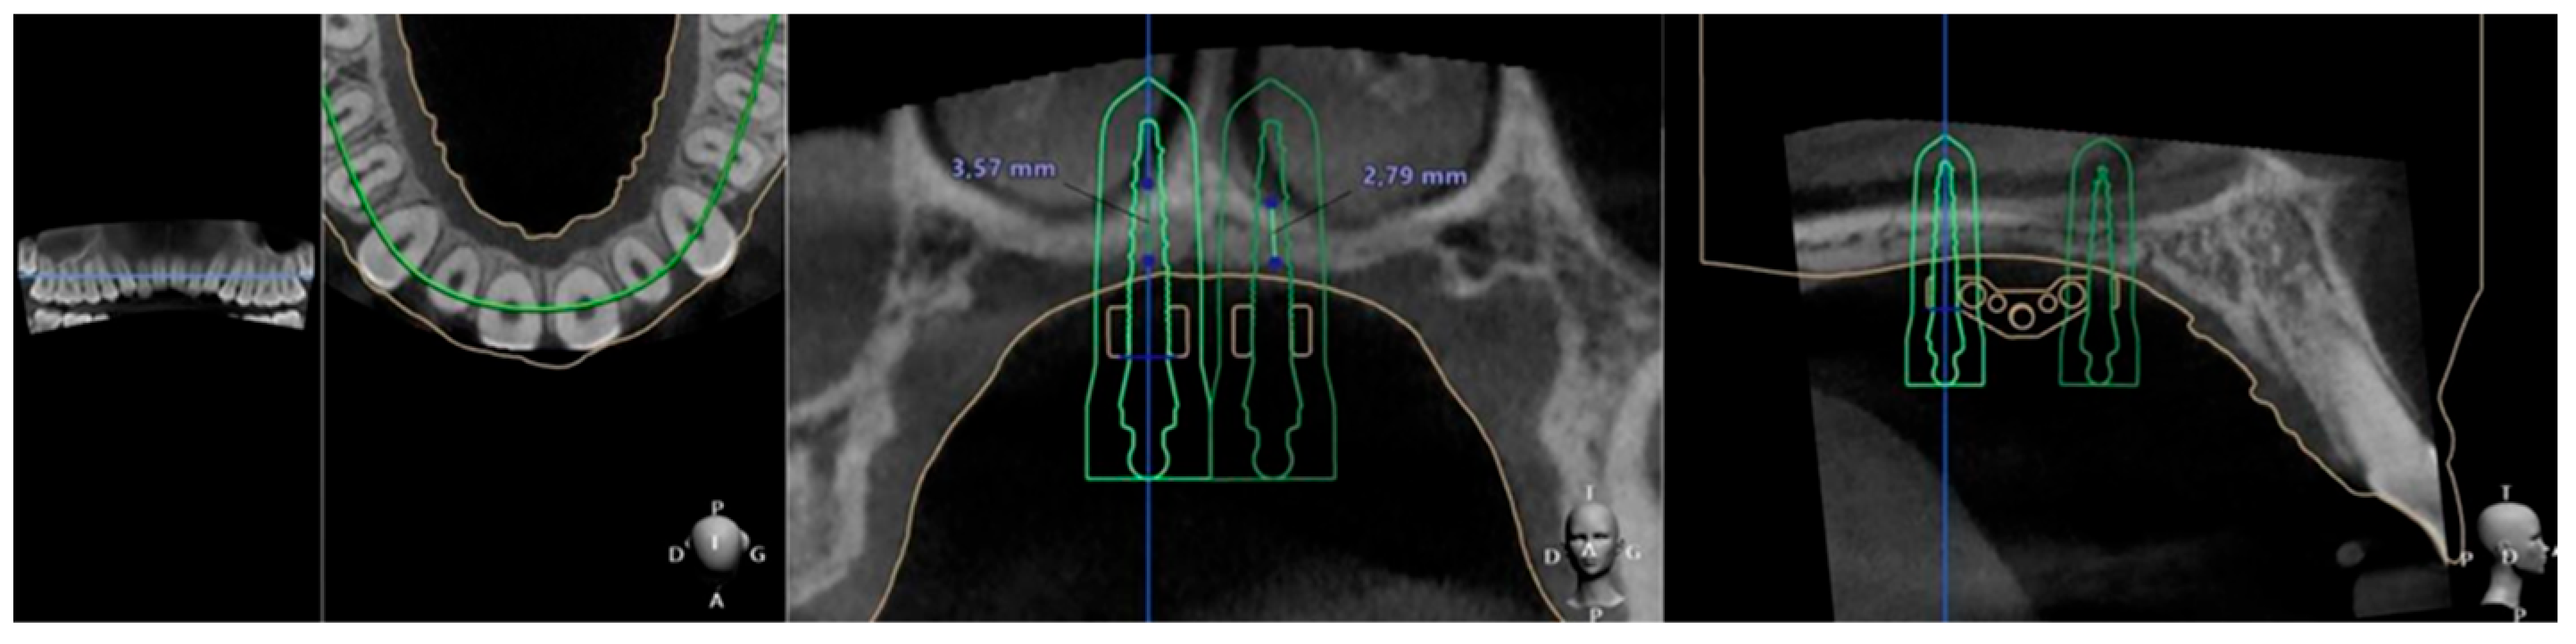

- The MSE system designed by Dr. Won Moon (Biomaterials Korea, Seoul, Republic of Korea) that has a jackscrew component with four parallel holes for mini-implant insertion and supporting arms on both sides soldered to the molar bands, aiming to stabilize the device’s position during expansion. Regularly, the position of the appliance is between the two zygomatic-maxillary buttresses, frequently located at the level of the first molars, so the mini screws are located just anteriorly to the soft palate [10,28]. An example of the posterior positioning of the MSE jackscrew with four mini-implants performed for a patient in our clinic, can be seen in Figure 2.